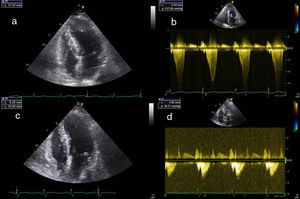

A redução imediata do gradiente não é atualmente considerada um objetivo essencial à eficácia do procedimento. Após ASA a obstrução evolui em três fases: logo após a administração intracoronária do álcool existe diminuição do gradiente por stunning do miocárdio, de seguida ocorre um agravamento da obstrução provocada pela fase de edema da região necrosada e que dura cerca de 5-10 dias, por fim dá-se a fase de cicatrização e remodeling, que se estabelece por volta dos três meses sendo ainda de esperar melhoria do gradiente até 12 meses após a intervenção15 (Figura 3).

Resultados ecocardiográficos após três meses. a) Ecocardiografia transtorácica quatro câmaras prévia à intervenção. b) Doppler contínuo mostrando gradiente subaórtico prévio à intervenção. c) Ecocardiografia transtorácica quatro câmaras, três meses após a intervenção, mostrando diminuição da espessura da porção basal do septo. d) Doppler contínuo três meses após intervenção mostrando diminuição do gradiente subaórtico.